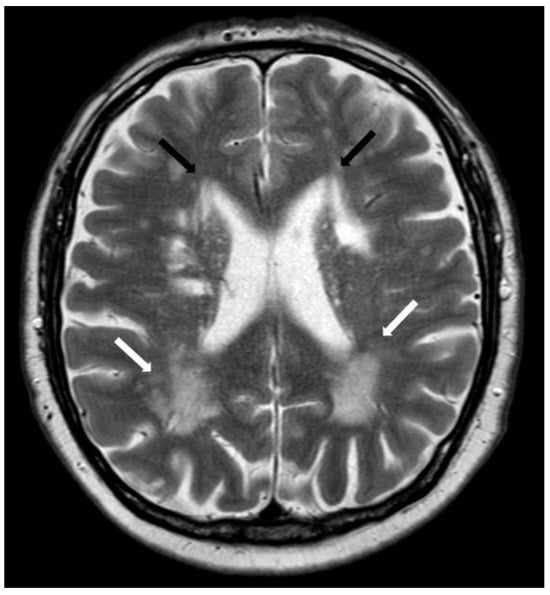

5.2.1. Enlarged Perivascular Spaces

- Charidimou, A.; Boulouis, G.; Pasi, M.; Auriel, E.; van Etten, E.S.; Haley, K.; Ayres, A.; Schwab, K.M.; Martinez-Ramirez, S.; Goldstein, J.N.; et al. MRI-visible perivascular spaces in cerebral amyloid angiopathy and hypertensive arteriopathy. Neurology 2017, 88, 1157–1164. [Google Scholar] [CrossRef] [PubMed]